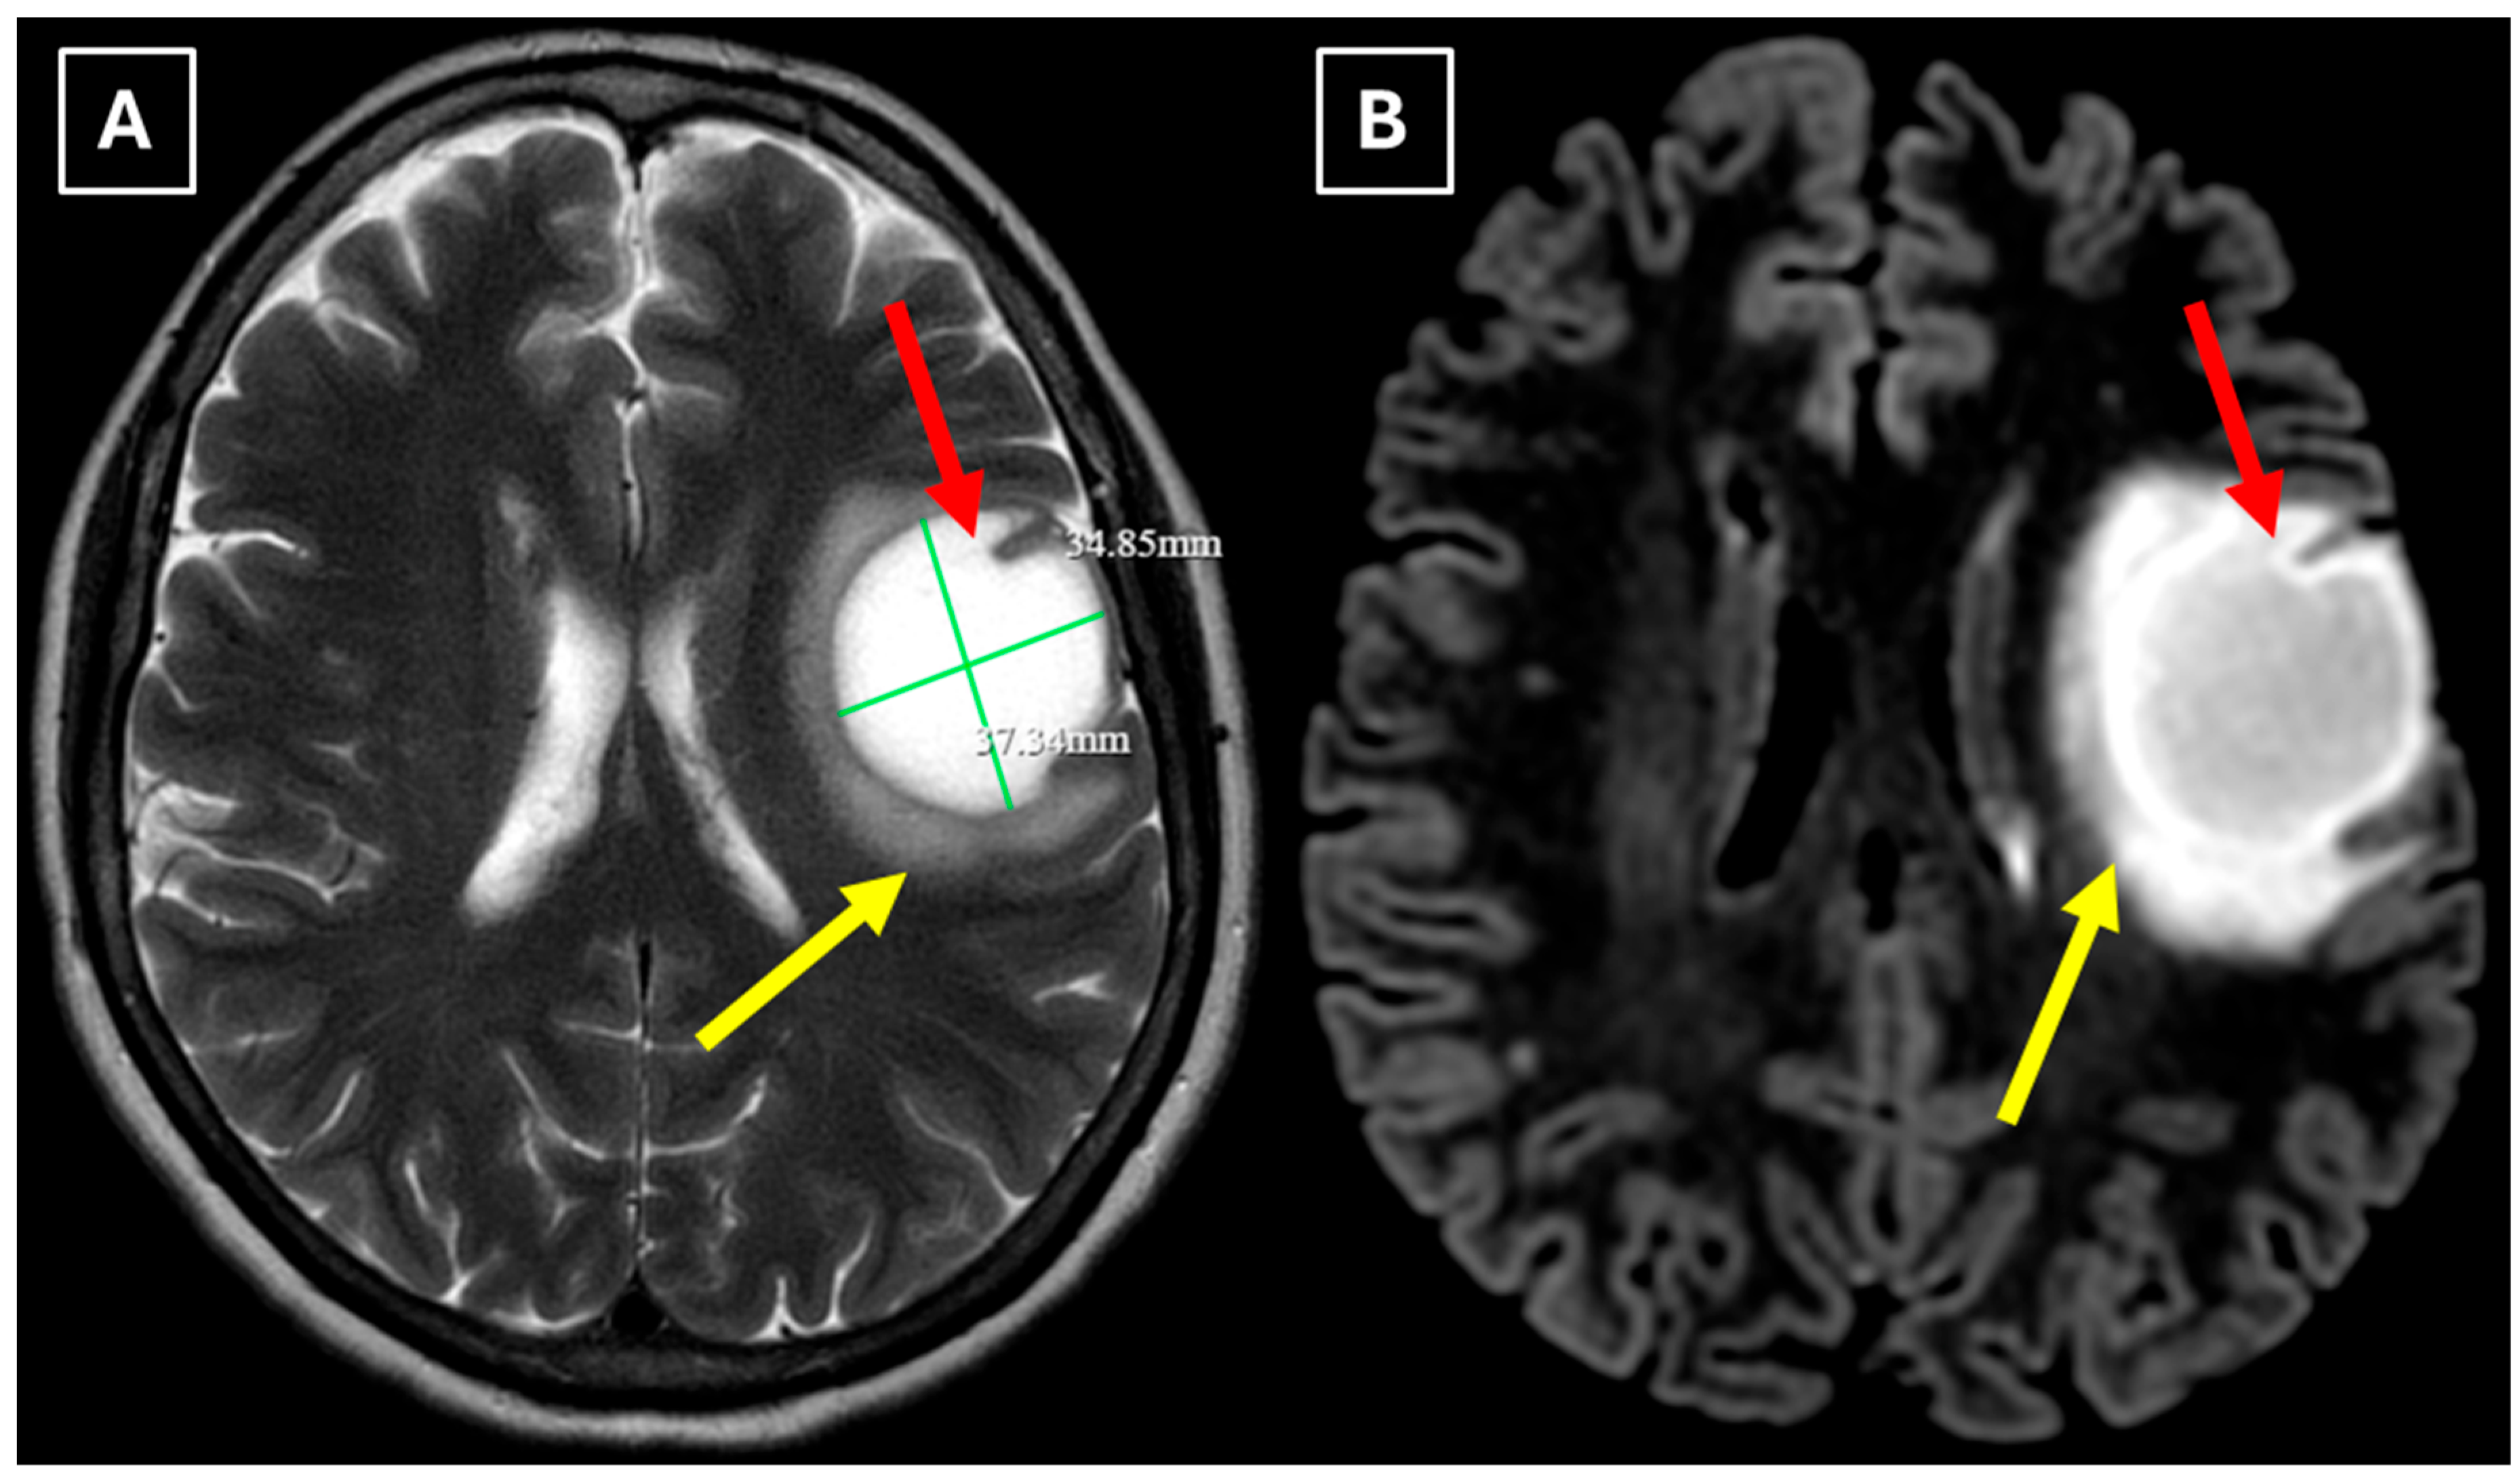

A repeat MRI before surgery showed that the lesion had reduced in size with no pathological contrast uptake persistence, with surrounding perifocal edema (Figure 4 and Figure 5). Given the improved results, the medical team suspected a demyelinating disease rather than a tumor and surgery was canceled. For diagnostic purposes, a lumbar puncture was performed. Cerebrospinal fluid (CSF) analysis excluded neuroinfection. Blood tests and CSF were examined according to the demyelinating disease protocol. Oligoclonal antibodies were negative in both the CSF and blood serum. Aquaporin-4 (AQP-4) antibodies were not found in the blood serum, and myelin oligodendrocyte glycoprotein (MOG) antibodies were also negative.

Figure 4. Two-week follow-up MRI scan of the brain. (A): Axial T2-weighted image shows a hyperintense and homogenous left frontal lobe lesion with well-defined borders. The lesion decreased from 37.34 mm × 34.85 mm (AP × LL) to 24.87 mm × 29.71 mm (AP × LL). A relatively extensive perifocal edema again persists, involving the white matter with relative spare of the white matter adjacent to gray matter; however, there is no mass effect or midline shift. (B): In the axial FLAIR the lesion appears with a more hypointense center and hyperintense peripheral rim at the lesion margins. Given the observed changes over a 2-week period and the decrease in the lesion’s size, an astrocytoma is considered less likely. Red arrow—indistinct formation, yellow arrow—perifocal vasogenic edema.

Figure 5. Two-week follow-up MRI axial scan of the brain. (A): Axial trace from diffusion-weighted imaging shows a higher signal along the peripheral parts of the lesion with the absence of cytotoxic edema when correlated with (B): the ADC map. (C): Central vein sign is positive on the susceptibility-weighted imaging sequence and (D): axial postcontrast T1-weighted sequence. These findings were not typical for low-grade astrocytomas. Red arrow—diffusion restriction, yellow arrow—perifocal vasogenic edema, green arrow—central vein sign.

Finally, we provide a high-resolution MRI follow-up of two months’ duration showing near-complete regression of the lesion after corticosteroid therapy. The lesion decreased from 37.34 mm × 34.85 mm (AP × LL) to 24.87 mm × 29.71 mm following two weeks of corticosteroid therapy and after almost two months from the first MRI scan to minimal patchy contrast enhancement (Figure 7D). This marked decrease in the size of the lesion gives strong evidence that a demyelinating rather than neoplastic process is present.

MRI findings alone can be misleading, but in correlation with the response to corticosteroid therapy, they may point towards a demyelinating process. TDLs may show significant reduction or near-complete resolution on follow-up imaging after corticosteroid therapy, suggesting their non-neoplastic etiology. As illustrated by the cases summarized in Table 1, similar observations in the literature have also been documented. Turkistani et al. (2018) [18] described a lesion with open-ring enhancement and moderate mass effect which initially suggested a glioma but underwent a decrease in size following corticosteroid therapy. Zafar et al. (2022) [19] documented a non-enhancing lesion in the parietal lobe without mass effect or other additional lesions, initially suspected to represent a low-grade glioma but which otherwise showed considerable radiological regression following corticosteroid therapy, thus suggesting its demyelinating origin.

In this case, despite the presence of a T2/FLAIR mismatch sign (Figure 2), several imaging characteristics were more suggestive of a TDL rather than IDH-mutant astrocytoma. The lesion was located in juxtacortical white matter and had cortical sparing, which is unusual for IDH-mutant astrocytomas, since they typically have been shown to infiltrate and expand the cortex. The diffusion restriction at the lesion margin with centrally elevated ADC values was more consistent with reported DWI findings of TDLs and contrasted with the central restriction often seen in gliomas. The mass effect was mild in comparison to the overall lesion size, favoring demyelination rather than neoplasm in this case. Additionally, the lesion had a central vein sign, as described above, a radiological sign supportive of inflammatory demyelination. The combination of cortical sparing, peripheral diffusion restriction, mild mass effect, and the appearance of central vein sign represented strong features that raised suspicion of a tumefactive demyelination lesion.

Follow-up MRI showed lesion shrinkage after two weeks (Figure 4) and by two months, near-complete lesion regression and resolution of perifocal edema. The radiological course was typical for TDLs and no alternative differential diagnosis appeared reasonable, as both the clinical response to therapy and MRI follow-up strongly supported the demyelinating origin. Thus, biopsy was not performed in this case. In the literature similar cases have been reported where biopsy was avoided, as the disease responded to treatment and imaging findings were consistent with a demyelinating process [27]. Moreover, biopsy of the brain in TDLs carries considerable procedural risks, including seizures and post-operative infections [2]. However, despite the lesion regression after corticosteroid therapy, which was supportive of a TDL diagnosis, the lack of biopsy confirmation represents a limitation in this case and warrants explicit acknowledgment of the risk of misdiagnosis, especially with lesions that have less certain regression.